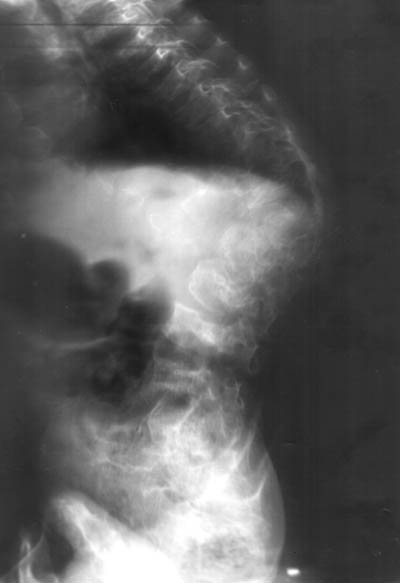

Девочка, 5 лет. Дз: спондилоэпиметафизарная дисплазия.Какое хирургическое лечение необходимо? Кто может принять на лечение?

A girl, 5 yrs old, living in Ukraine, needs an orthopaedic treatment due to subj.Can anybody tell, what kind of surgical corrections must be made now, and what are possible later.It is also important to know, what hospitals in Eastern Europe are the best to manage with that.Best regards,Andrew Yurtseniuk,orthopaedic surgeon,Chernivtsi, Ukraine

in spondyloepiphyseal dysplasia very rarely surgical corrections should be done (for example the epiphyseal dysplasia of the hip joints should not be treated like Perthes which looks similar than should be tretated conservatively).

In this special case the spine has to be treated and i would start with a brace (soft boston brace) to prevent further deformity of this kyphosis.

i would try to keep a good rom of all joints and buy time, i would discuss to perform an MRI investigation of the spine and the hips.